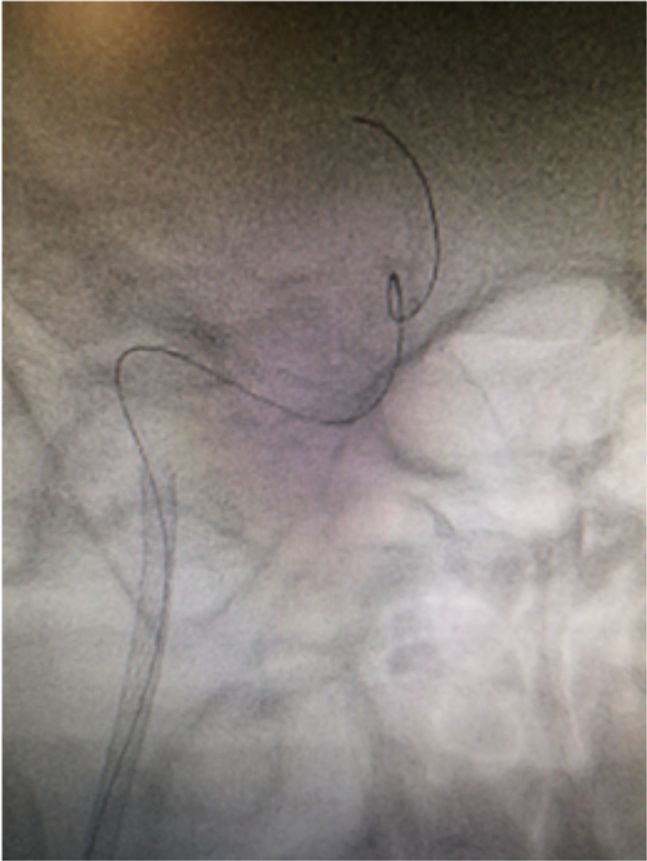

常规消毒铺巾,右侧股动脉穿刺成功,置入9F动脉鞘。150 cm超滑泥鳅导丝携5F单弯造影管分别行双侧颈总、左侧椎动脉正侧位造影,结果显示右侧颈内动脉C1-C4段闭塞,右侧颈外动脉侧枝向右侧眼动脉代偿供血,并反流至右侧颈内动脉颅内段,右侧大脑中、前动脉显影变淡(图5)。14∶50肝素4 000单位入壶,在长交换260 cm泥鳅导丝导引下将MOMA先端置于右侧颈外动脉,撤出泥鳅导丝。路径图下,PILOT50微导丝(0.014"x190 cm)携带Headway 21微导管沿MOMA送入右侧颈内动脉,微导丝通过闭塞段,微导管通过困难(图6)。

图5

图6